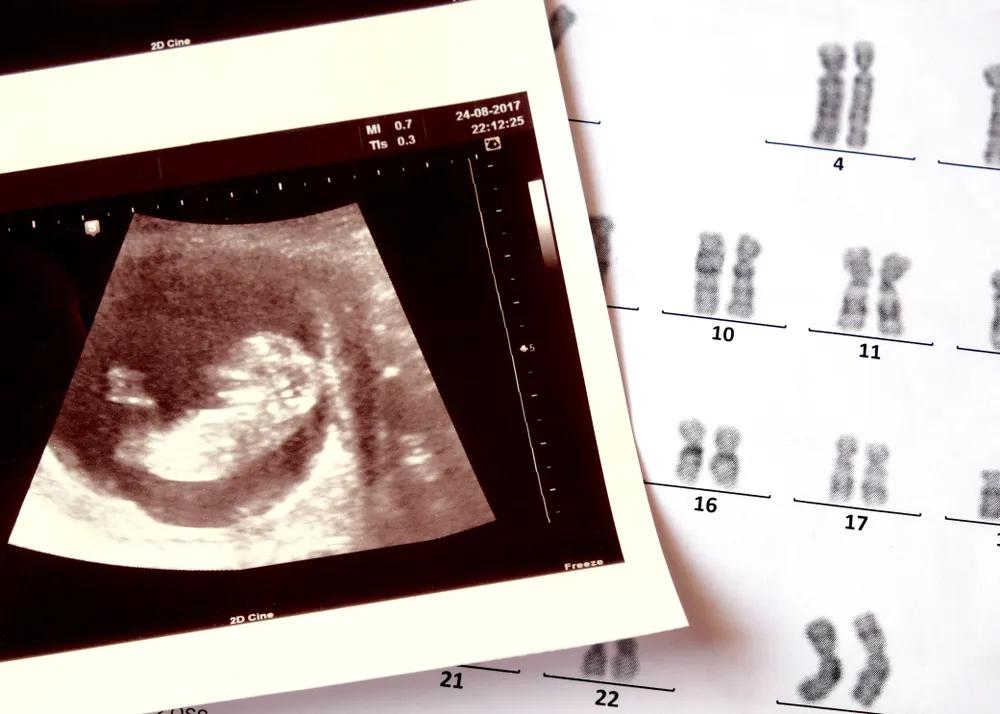

图源:站酷海洛